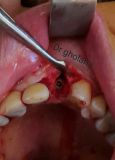

معرفی سیستم SPI همراه با جراحی زنده و Immediate Loading - آبان ۹۵

جراح وسخنران : استاد دکتر غلامعلی غلامی